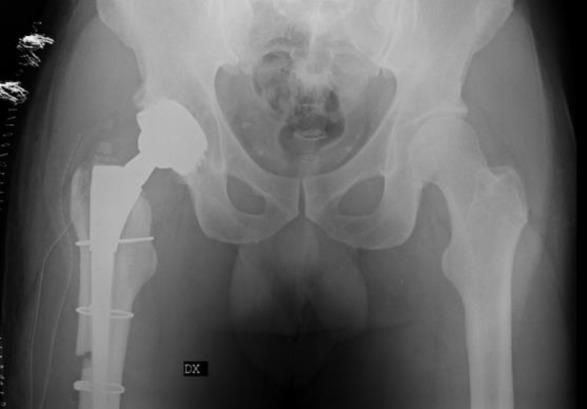

模块化牢固固定型髋关节翻修柄骨折:一例报告及文献综述

Modular Well-Fixed Hip Revision Stem Fracture: A Case Report and Literature Review.

This study presents a case of repeated prosthetic fractures in a modular hip prosthesis in a 56-year-old male patient. After the initial implantation of a modular total hip prosthesis in 2006, the patient experienced two instances of prosthetic implant fractures over seventeen years. In this study, we analyze the clinical case, explore potential underlying causes of this complication, and delve into current indications and strategies for the revision of fractured prosthesis stems. The discussion is informed by a literature review and underscores the significance of selecting appropriate revision techniques to address this challenge.

摘要

本研究报告了一例56岁男性患者模块化髋关节假体反复发生假体骨折的病例。2006年首次植入模块化全髋关节假体后,该患者在十七年中经历了两次假体植入物骨折。在本研究中,我们分析了该临床病例,探讨了这种并发症的潜在根本原因,并深入研究了目前骨折假体柄翻修的适应症和策略。讨论以文献综述为依据,并强调选择合适的翻修技术来应对这一挑战的重要性。